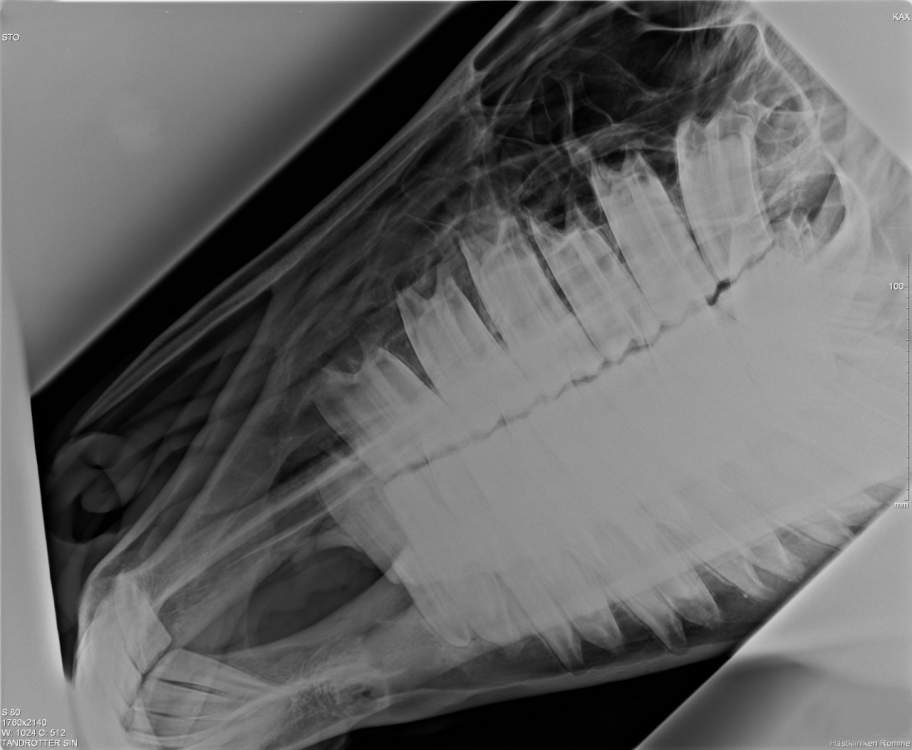

Tack vare en mycket kraftfull röntgengenerator, synkroniserade takhängda raster och den digitala framkallningsteknologin kan vi idag erbjuda alla röntgenundersökningar som tillämpas på häst. Prestandan på utrustningen och många års erfarenhet samt kontinuerlig vidareutbildning gör att vi kan utföra och tolka röntgenundersökningar av t.ex. huvudet/tänder, halskotpelarna och ryggen, höga leder som bog och bakknä samt få extra detaljrika bilder på svåra områden som hovar m.m.